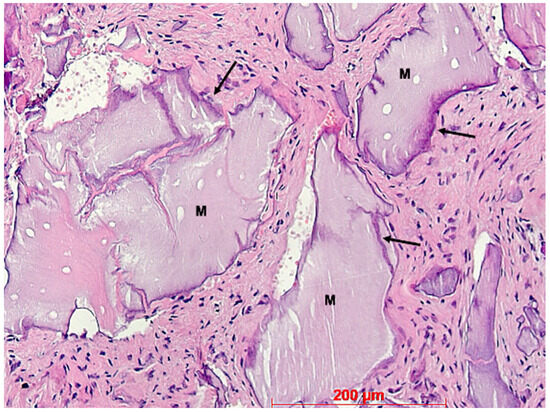

3. Results